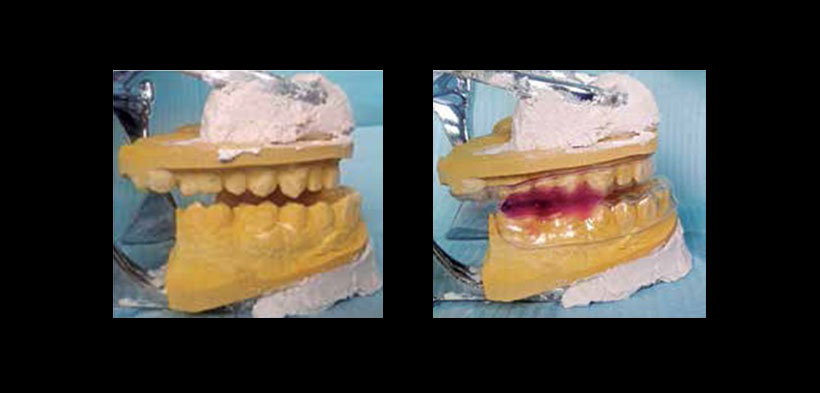

Fig. 1. Modelos de estudio para confección de dispositivo de avance mandibular.

Fig. 2. Aparatología de avance mandibular, en la figura se muestra el dispositivo colocado en boca, nótese el avance mandibular.